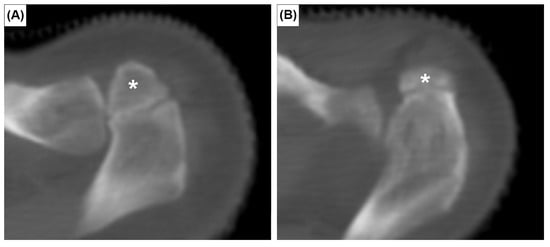

The EOs were present at the posterior surface of the manubrium in 12 cases (2.0%). It was unilateral in seven sterna (58.3%) (Figure 2A,B) and bilateral in five (41.7%) (Figure 2C). The CR was found bilaterally in one patient (0.2%) (Figure 3). In this patient, the left CR was approximately 40 mm long and did not articulate with any other structure. The right CR was approximately 60 mm long. It coursed anteriorly and inferiorly to reach the manubrium, but did not articulate with it.

Figure 3. Coronal (A), axial CT images (B) and three-dimensional reconstruction of right (C) and left (D) cervical ribs. Red arrowheads and asterisks indicate the cervical ribs.